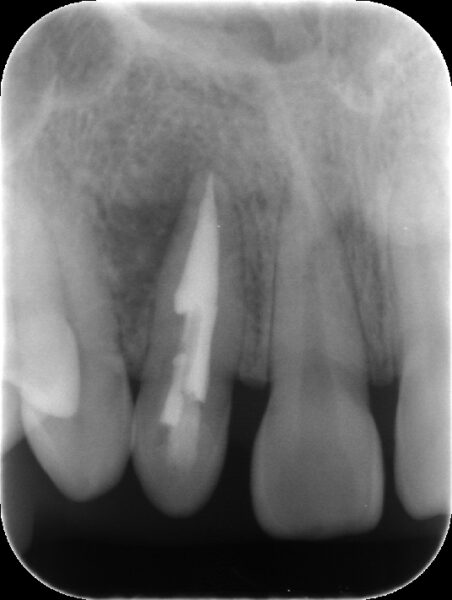

【術直後のレントゲンと口腔内写真】

2本の根管に緊密に根管充填材(MTA)が充填出来ていることが確認できました。

【経過観察時(術後3か月後)レントゲン】

術後3か月後のレントゲンでは黒くなっていた部分が回復してきており、骨が再生してきていることが認められました。